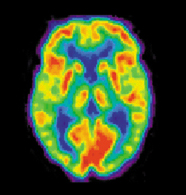

PET imaging has been widely used by neuroscientists to better understand what areas of the brain are activated for a variety of mental tasks and for diagnosis of brain diseases. An example of the latter is shown below in Figure 18. Two brain scans demonstrate drastically different levels of metabolic activity between a normal brain and that of an Alzheimer’s patient.

(a)PET scans of a normal brain.

(b)PET scans of an Alzheimer’s Disease brain.

Figure 18:Image from http://